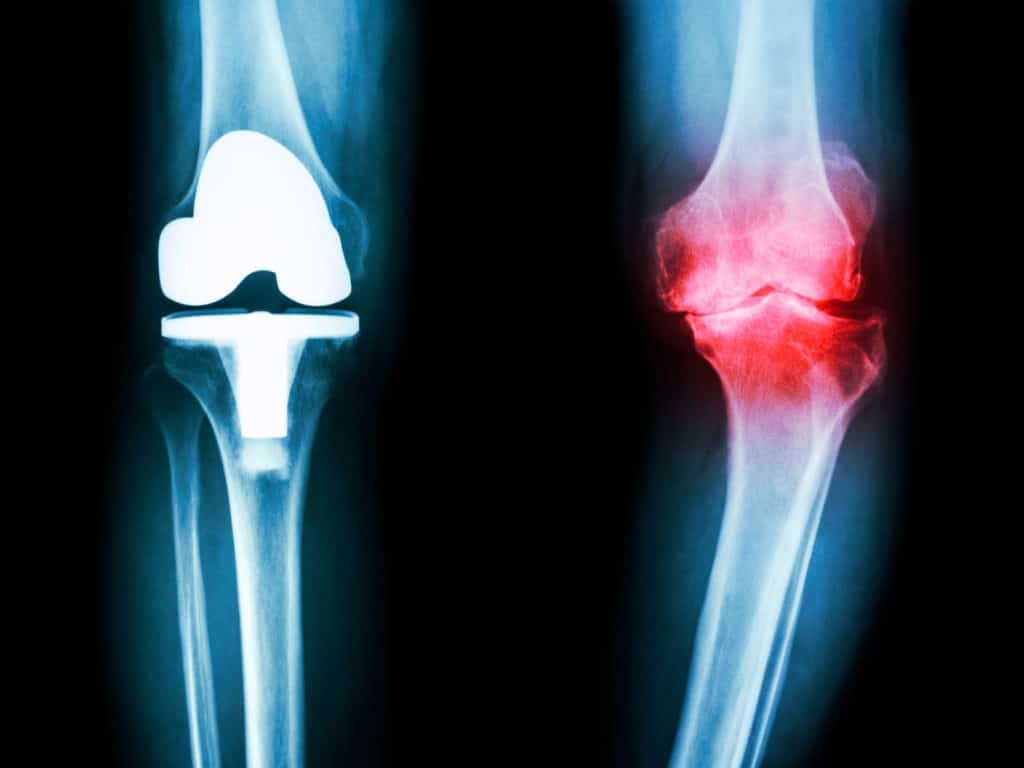

帮助患者尽最大脚 写道 多伦多大学吉莉安·霍克博士正在帮助潜在的膝关节置换患者对其健康做出明智的决定。由于我们越来越多的人需要联合更换,霍克斯博士寻求确保只有最适合的人会接受手术。通过开发用于膝关节外科的标准化患者评估标准,霍克斯博士致力于[...] 阅读更多…